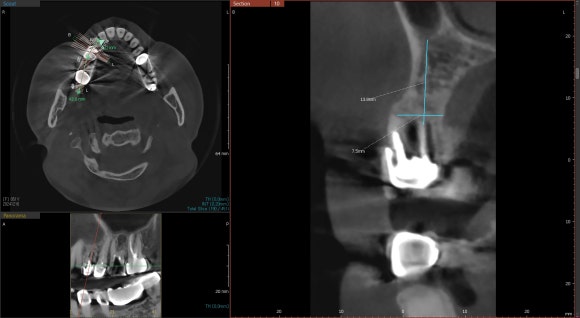

20240120

치아를 둘러싼 염증이 심하신 편이 아니어서

(=깨끗하고 감염이 없는 뼈조직)

치아를 발치하면서 동시에

임플란트를 식립하였습니다.

뼈가 얇고 좁은 환자분들은

시간이 지남에 따라 뼈가 흡수되어

주저앉는 경우가 많기 때문입니다.

수술 후 반드시 CT를 촬영하여

원하는 위치에, 원하는 방향으로

임플란트가 제대로 식립되었는지

확인하는 것이 중요합니다.

눈으로 볼 수 없는 곳까지

꼼꼼하게 체크하는 과정입니다.

임플란트를 원하는 위치에 정확히 식립하는 것은

술자의 경험과 공간지각력에 의해

크게 좌우됩니다.